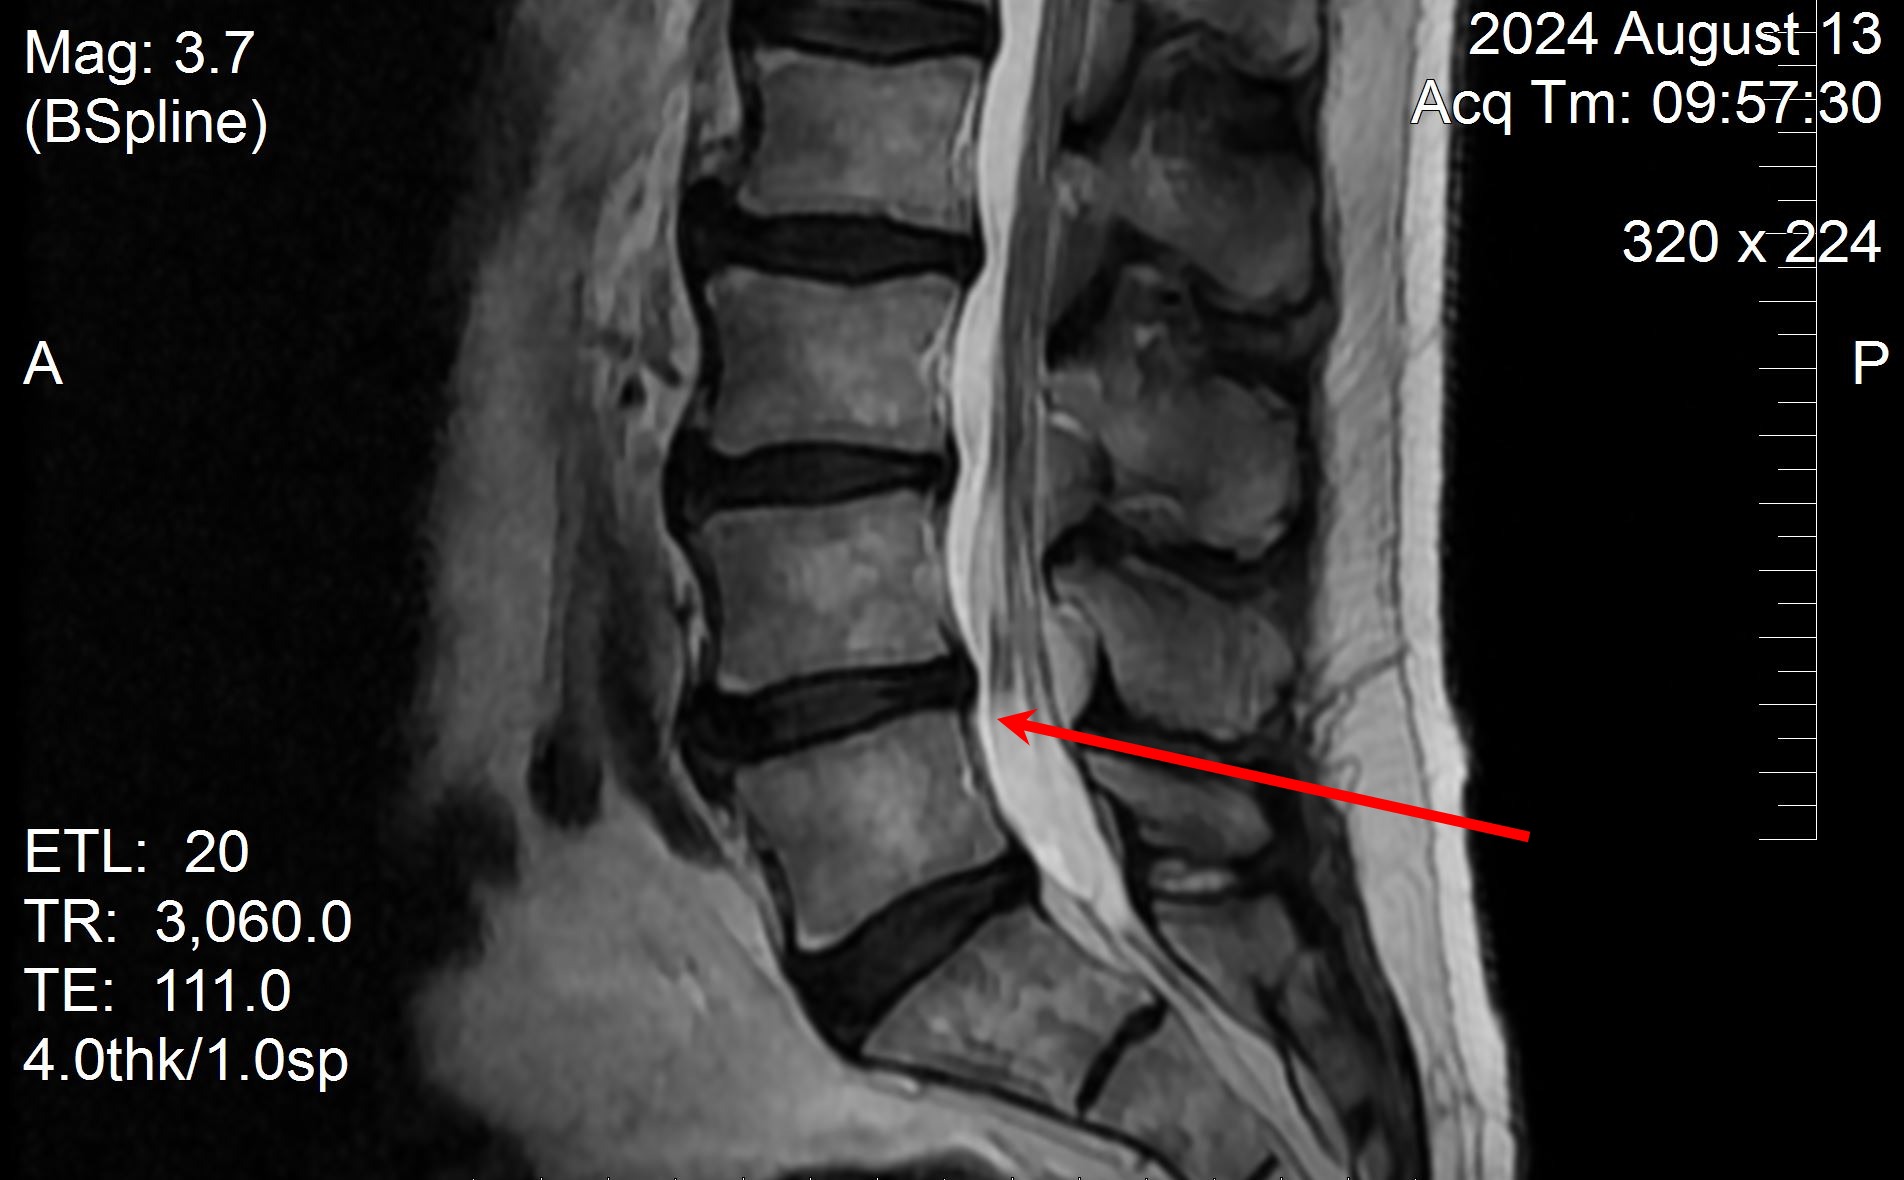

Based on evidence, large disk herniations start to regress by a few millimeters (mm) within 10 days of receiving our proprietary treatments. In this example below, a large disc herniation was found to be compressing on the lower part of the spinal cord called cauda equina causing severe pain symptoms in the patient (Left Image, red arrow). Within 7 days of a SINGLE treatment (treatment date 12/7), the large disc herniation had regressed releasing the free floating fibers of the cauda equina (Right Image, red arrow). The patient not only got immediate pain relief but also effectively avoided surgical treatments, such as open laminectomy and the adverse events that may follow such surgical treatments. Additionally, multiple treatments and repeat injections are NOT required for this specific disc herniation, as the herniation will continue to regress without repeat treatments

By August 2024, MRI of the above patient showed complete resolution (dissolution) of the disk herniation with official radiology reading saying, “the previously visualized disk protrusion (herniation) is no longer visualized.”